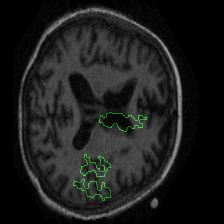

Figure 1 presents attribution maps generated using PWIG for a selection of MRI scans across all four diagnostic categories. The highlighted regions (in green) correspond to the areas that contributed most significantly to the model’s decision. Notably, we observe consistent emphasis on anatomical structures that align with clinical markers of dementia, including cortical and subcortical regions. For instance, in the moderate and mild dementia examples, the model focuses on regions exhibiting visible atrophy or abnormal morphology. In contrast, attribution maps for non-demented subjects appear more diffuse and less concentrated, reflecting the model’s detection of normal anatomical patterns.

The results in Figure 1 demonstrate that PWIG can effectively produce interpretable and clinically meaningful explanations for model predictions in medical imaging tasks.

Figure 1: PWIG attribution maps across dementia categories using the OASIS-1 dataset. Green overlays indicate regions with the highest attribution scores.